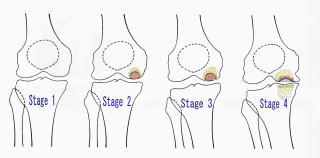

膝蓋骨脱臼の進行や軟骨障害

膝蓋骨脱臼で初回脱臼後10年以上になると、脱臼力も強くなり軟骨の障害例が多くなります。軟骨障害が進むと元通りに回復させることは難しく脱臼は治っても軟骨の痛みが残りますので早めに手術を受けて下さい。初回の脱臼の平均は14~18歳頃ですので手術せずに30歳代になるとこのような状態になります。

症状は、通常の変形性関節症と似た所見を呈しますが、初期に夜間安静時に急性に疼痛が発症することもあります。初期にX線上明らかでない時期(stage 1)があり、『軽い変形ですのでじきに治ります』といわれることが多くあります。しかし、痛みが長引き、さらには骨壊死部が柔らかくなり、道路の陥没と同じように、関節面が陥没を始めると非常に痛みが強くなってきます。

診断

腰野のX線分類が有名です。

Stage 1 (発症期): X線上病的所見を認めない時期。

Stage 2 (吸収期): 半円形の骨透亮像(吸収像)や顆部がやや平坦化像を呈し骨壊死部が線維化しつつある時期

Stage 3 (完成期): 骨透亮像を骨硬化像(sclerotic halo)が囲み底部に石灰板が形成され陥没が進行している時期

Stage 4 (変性期): 骨壊死部の陥没が進行して、明らかな変形性関節症となった時期

なかなか理解しがたい病気ですが、例えていいますと道路の下水道管が破裂して水が出てしまった状態に似ています。水道管の破裂が大きいと急な痛みが出ますが、徐々にですと変形性関節症と類似します。進行具合は出た水の量によると考えて下さい。出た水が少しですと陥没を起こさず治癒しやすくなりますが、水が多量に出ますと土が軟らかくなって時間が経つに従い、陥没していきます。

Bruckl分類

離断性骨軟骨炎の病期は関節面に繰り返しかかるせん断力が軟骨と下の骨(軟骨下骨)の間で、剥離骨折を生じ(I,II)、さらに悪化するとその周囲が壊死をきたし(III,IV)、ついには軟骨がわずかな軟骨下骨をつけて剥離(V)へと進みます。したがってX線もその段階を示唆するBrucklの分類が有名です。

Brucklの分類 Stage I:X線で異常なし Stage II:病巣部の骨透亮像 Stage III:病巣周辺に骨硬化像

Stage IV:病巣の硬化像と不安定性の進行 Stage V:遊離体